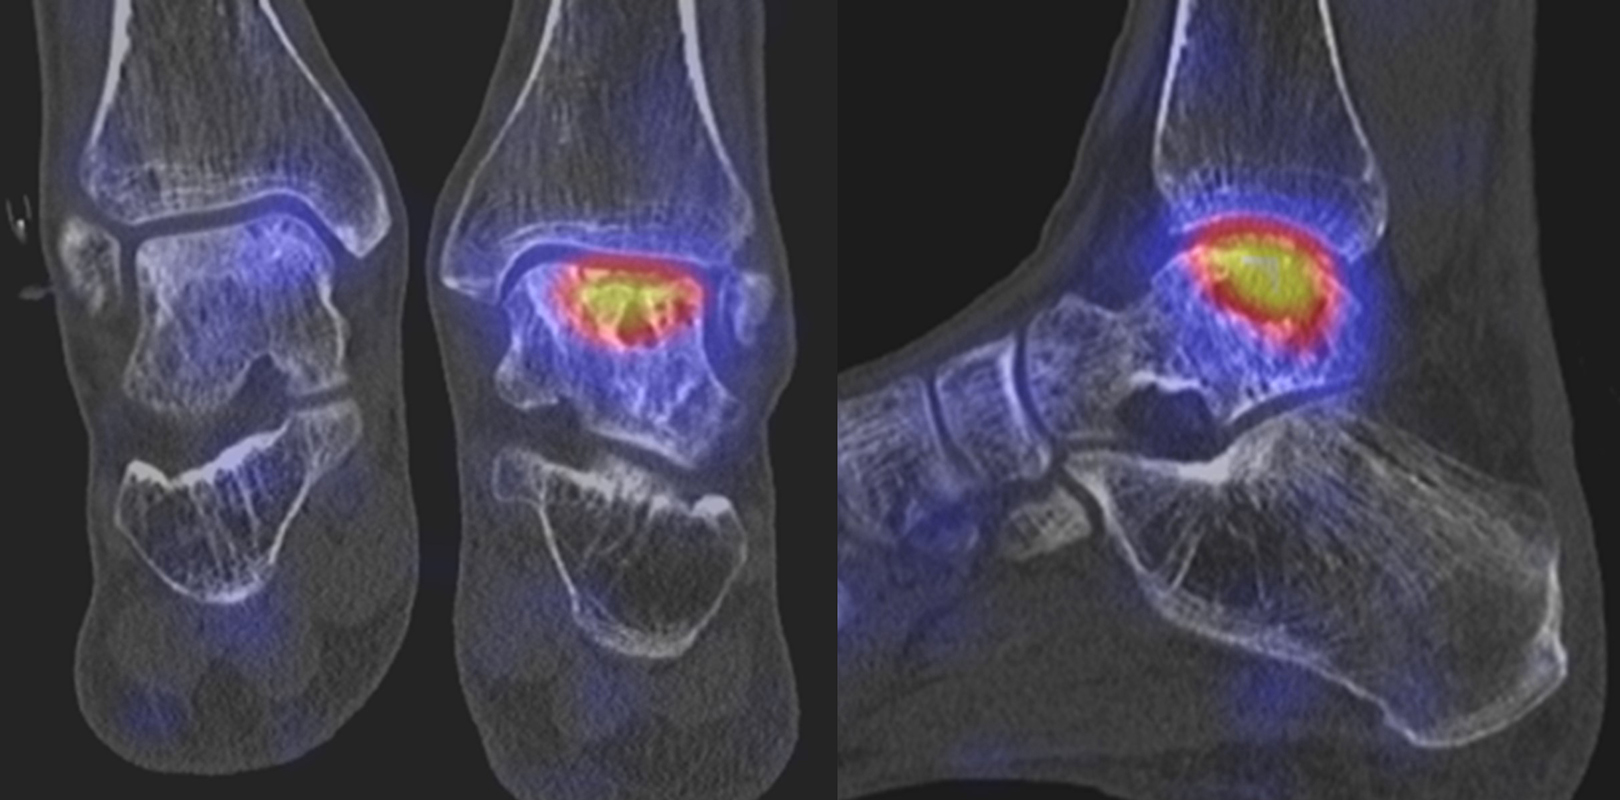

Abbildung 1.2. zeigt eine ausgedehnte posttraumatische Arthrose im linken OSG. Der metabolische Focus liegt in der Hauptbelastungszone.

Zum Lesen der Bildbeschreibung und zur Vollansicht bitte die Bilder anklicken. Bilder: H. C. Rischke

Abbildung 1.3.a und Abbildung 1.3.b: Der Patient hatte einen Skiunfall vor 40 Jahren mit distaler Tibiatrümmerfraktur. Nachfolgend Entwicklung einer Osteomyelitis; Operation mit Implantation eines Knochenspans. Klinisch rezidivierende Schwellungen des oberen Sprunggelenkes, bekannte Tibiafehlstellung. Frage nach Osteomyelitis, Status der Arthrose. Man sieht in Abbildung 1.3.a in der distalen Tibiametaphyse im CT Strukturveränderungen, die zu einer abgelaufenen Osteomyelitis passen - szintigraphisch hier keinerlei Anreicherungen und somit kein Infektverdacht, jedoch Nachweis einer aktivierten oberen und unteren Sprunggelenksarthrose.

Abbildung 1.4.a und Abbildung 1.4.b: Klinisch Verdacht auf talonaviculare Anschlussarthrose links bei Z. n. Fraktur im Bereich des linken Sprunggelenkes vor 17 Jahren. und Z. n. Oberschenkel-Unterschenkelfraktur vor über 40 Jahren. Obwohl auch CT-morphologisch im OSG arthrotische Veränderungen bestehen, ist nur die Arthrose im USG metabolisch aktiv bzw. als Ursache der Schmerzen einzustufen. Im Bereich des Talonavicular-Gelenkes - entgegen der klinischen Verdachtsdiagnose - kein erhöhter Metabolismus.